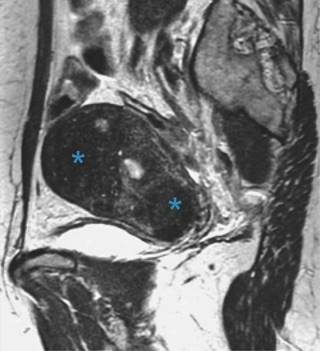

Adicionalmente, los hallazgos por resonancia magnética pueden ser clasificados como signos directos o indirectos. Dentro de los directos se encuentran los microquistes, siendo éstos el principal signo de adenomiosis identificable por resonancia magnética, los cuales tienen un tamaño de entre 2-7 mm, con una media de 3 mm y se encuentran dentro del miometrio (Figura 3),10 además de que se hallan principalmente en la zona de unión y raramente en el miometrio; son hipointensas en T1 e hiperintensas en T2, e identificables de mejor manera al final del periodo menstrual con cavidad quística.11 Los adenomiomas que se encuentran como una consolidación focal de las glándulas adenomióticas dentro del miometrio se manifiestan como una masa de paredes bien delimitadas en la zona de unión, por lo que el principal diagnóstico diferencial es el leiomioma uterino, ya que ambas presentan el mismo grado de intensidad, con la única diferencia que la vascularidad de los adenomiomas presenta más angiogénesis (Figura 4).12

Figura 4: Imagen sagital T2 de alta resolución en paciente con adenomiosis. Útero aumentado de tamaño en el que se visualizan zonas de adenomiosis focal (*) marcadamente hipointensas respecto al parénquima normal que queda entre ambas. En el espesor del miometrio engrosado en fundus, visibles varios focos hiperintensos que representan degeneración quística y glándulas ectópicas.